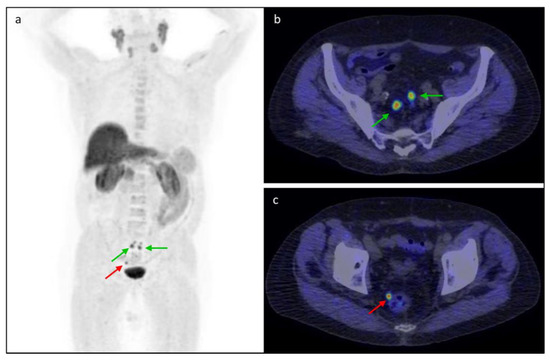

3.5. Clinical Cases